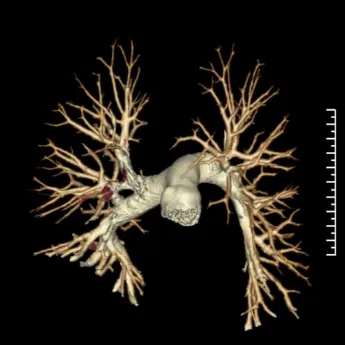

②影像学检查:CT肺动脉造影(CTPA)扫描速度快,图像可以多方位重建,能清晰显示血栓位置,是确诊肺动脉栓塞常用的方法。影像表现如图所示:

正常肺动脉